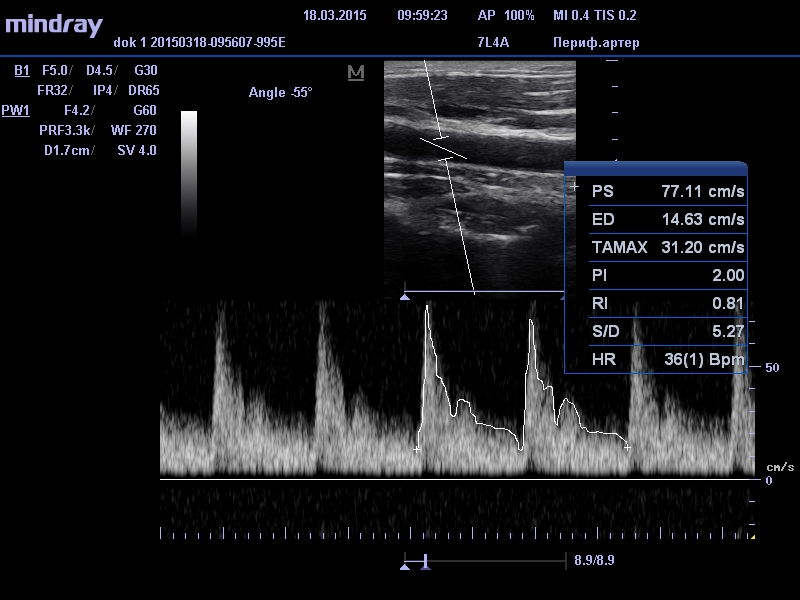

В это время на мониторе УЗИ сканера появляется изображение сосудов в разных режимах работы прибора. Диагност определяет толщину стенок, сужение или расширение участков сосудов, состояние их просветов (наличие атеросклеротических бляшек, а также возможных тромбов, их форму и размеры), имеются ли изгибы сосудов и их степень выраженности, аномалии развития. Большое значение имеет определение интенсивности кровотока и наличие нарушений кровообращения в определенных отделах головного мозга.